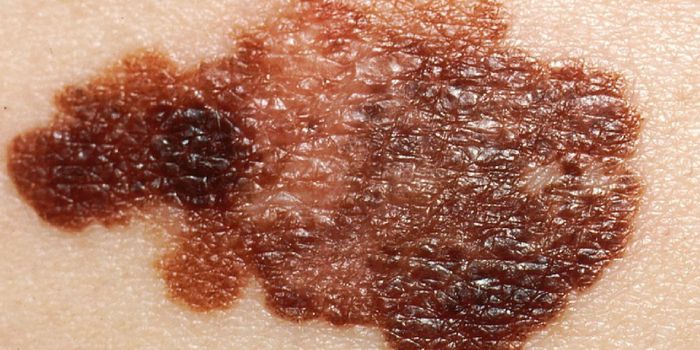

AUG 01, 2017CancerMelanoma, the most dangerous form of skin cancer, seems to be an opportunistic striker. Earlier this year, scientists co ...

AUG 30, 2017CancerThe next time you inspect your body for signs of skin cancer, pay special attention to new moles that were not there the ...

JAN 05, 2017CancerA large portion of melanoma cases prove fatal because the disease has already progressed beyond treatment options. Howev ...